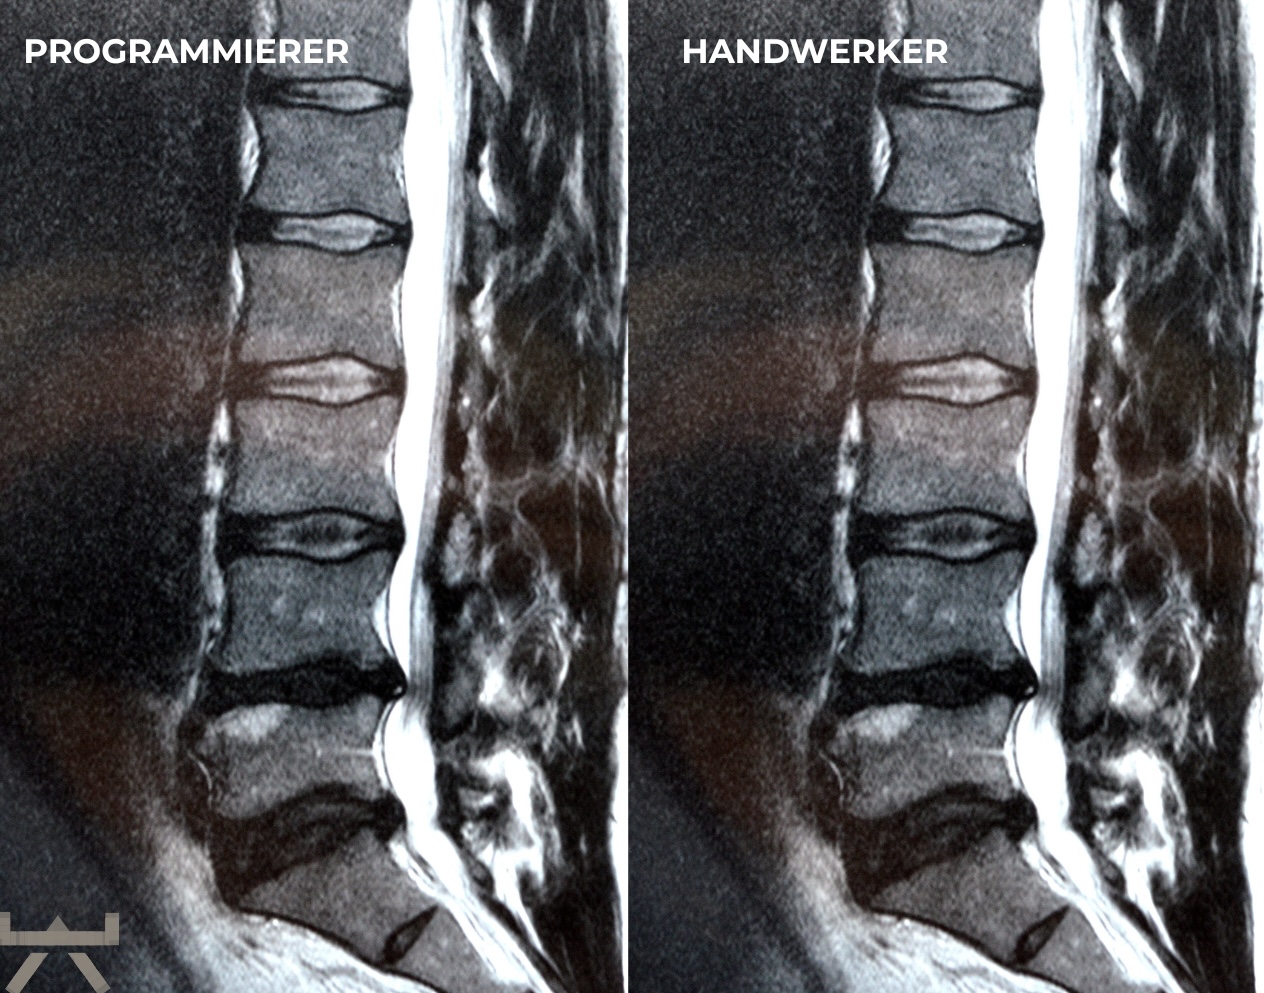

Arthrose wird durch schwere Arbeit verursacht.

Viele machen ihre Arbeit oder ihren Sport für Arthrose verantwortlich, obwohl die meisten Forschungsergebnisse feststellen, dass unsere beruflichen und freizeitlichen Aktivitäten einen relativ geringen Einfluss auf strukturelle Veränderungen haben. Eine der interessantesten Möglichkeiten, dies zu demonstrieren, sind MRT-Studien an schmerzfreien genetisch eineiigen Zwillingen, die aber sehr unterschiedliche berufliche und freizeitliche Aktivitätsniveaus haben, und trotzdem sehr ähnlich aussehende Scans aufweisen. Studien zeigen uns diesbezüglich, dass eine Wirbelsäule, die den größten Teil des Tages sitzt, jener bemerkenswert ähnlichsieht, welche den ganzen Tag schwere Arbeit leisten muss. 11